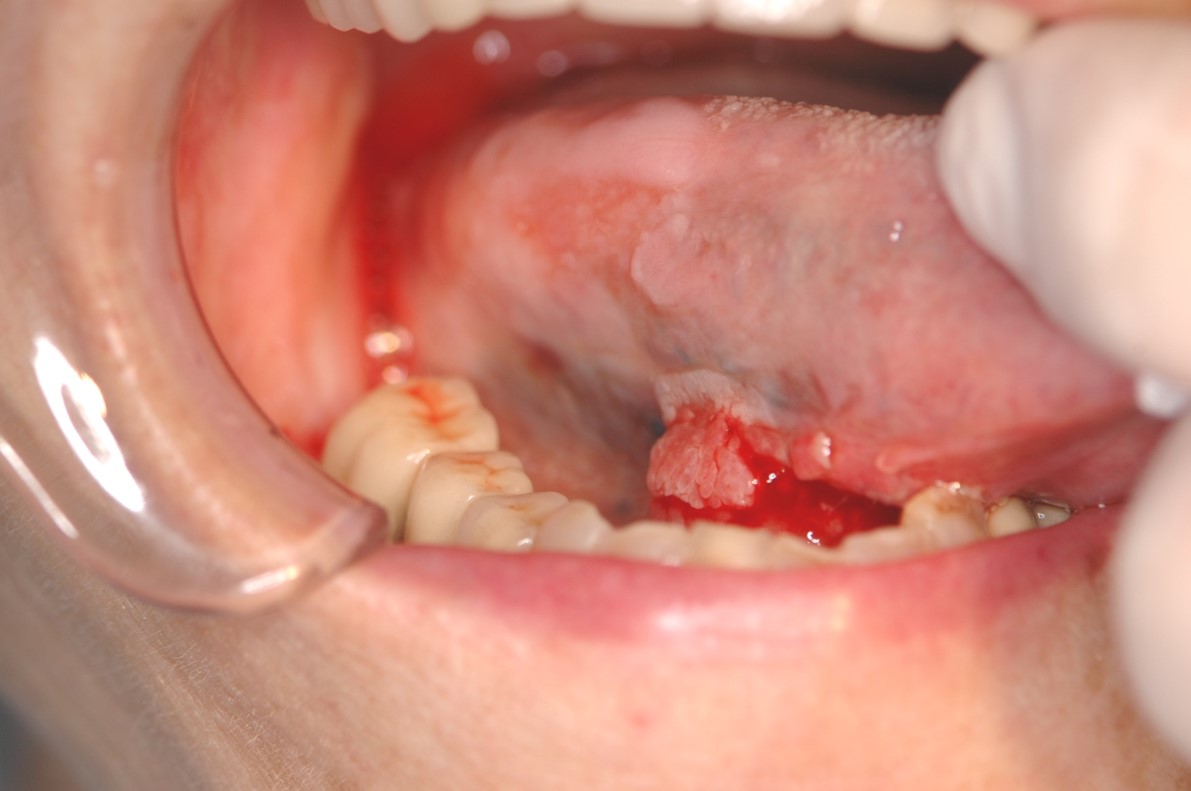

どこかわからないが、出血する

がんにより出血する場合があります。出血により、がんが見つかることも多いのです。歯周病による出血もありますが、重要な症状です。